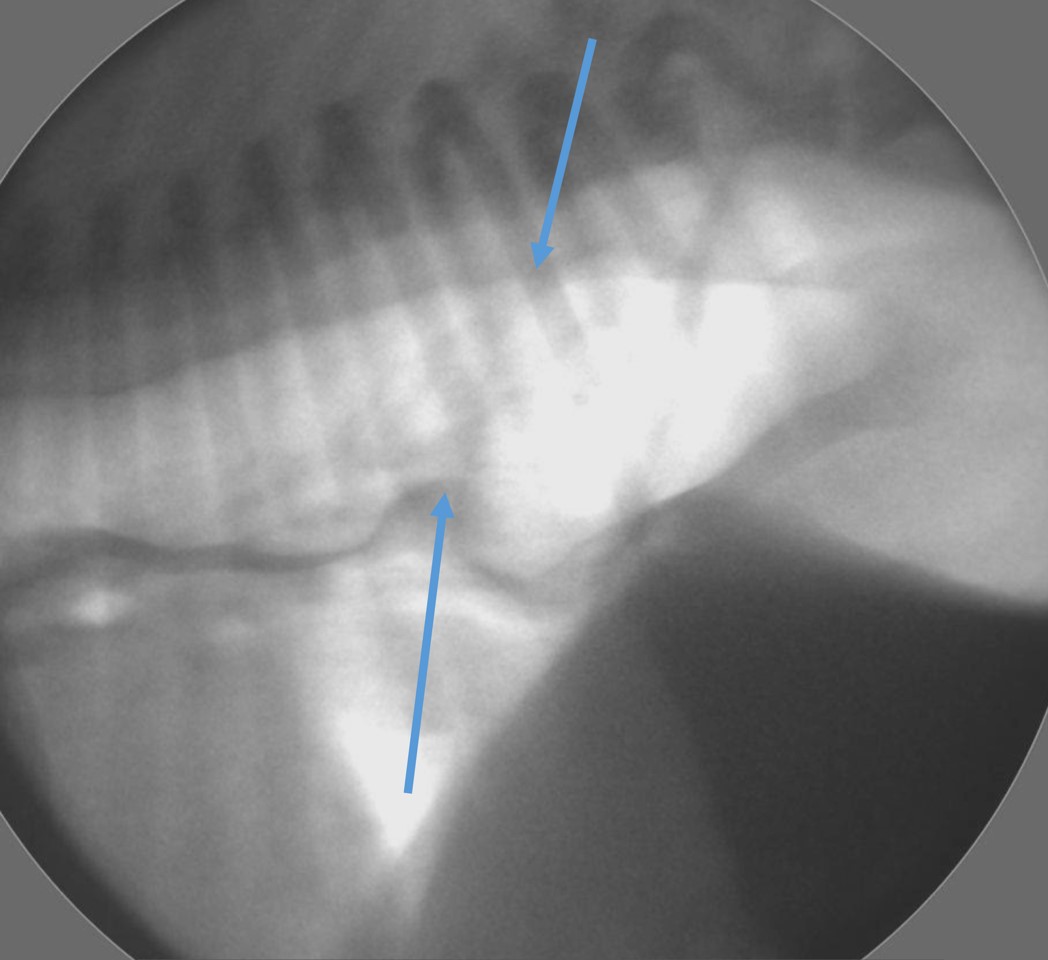

Hiatal hernias can be difficult to diagnose as they can reduce spontaneously and can sometimes appear normal when imaging is performed. This condition is normally diagnosed with a variety of techniques including fluoroscopy, where your pet is given food mixed with a dye which can then be observed moving through their upper gastrointestinal system. Another procedure that can help diagnose Hiatal Hernias is an endoscopy, where a camera is inserted into the oesophagus to see if the hernia can be seen directly.